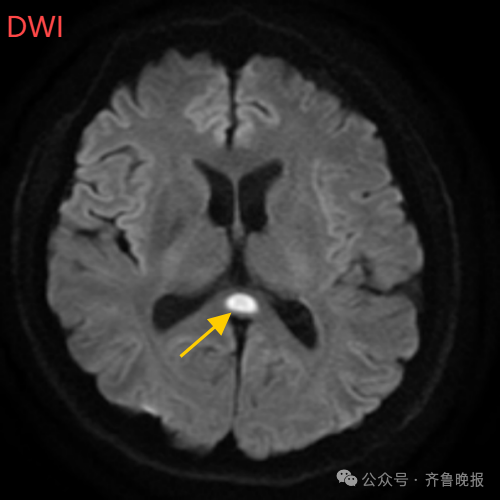

医生摇摇头,经过头部磁共振平扫、弥散、增强影像等检查,医生诊断,小董是得了一种比较少见的病症:可逆性胼胝体压部综合征。

640 (4).png

小董的影像结果显示,胼胝体压部发生病变